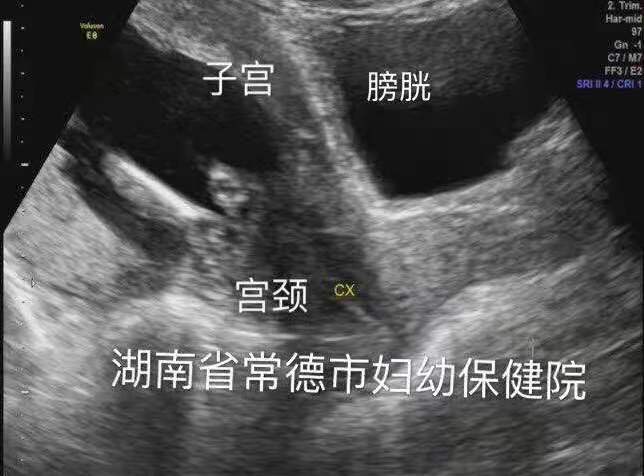

时间回到前一天。4月5日上午,何女士起床后发现自己排尿困难,并且下腹持续性胀痛,在丈夫的陪同下,夫妻俩来到常德市妇幼保健院就诊。产科主任杨御华见何女士左手按着下腹部且面色痛苦,便优先接诊了何女士。经检查后怀疑是“尿潴留”,迅速开具了B超单并标明加急,第一时间为何女士安排了B超。经影像诊断科童立里副主任医师B超检查:膀胱过度充盈,子宫明显后倾后屈位,宫内见胎儿回声,胎心胎动存在。确诊子宫箝闭症。

膀胱明显充盈表现细长,后方见妊娠子宫回声

子宫明显后倾后屈,宫颈细长

尿潴留缓解,子宫位置已转前位,宫颈远离尿道